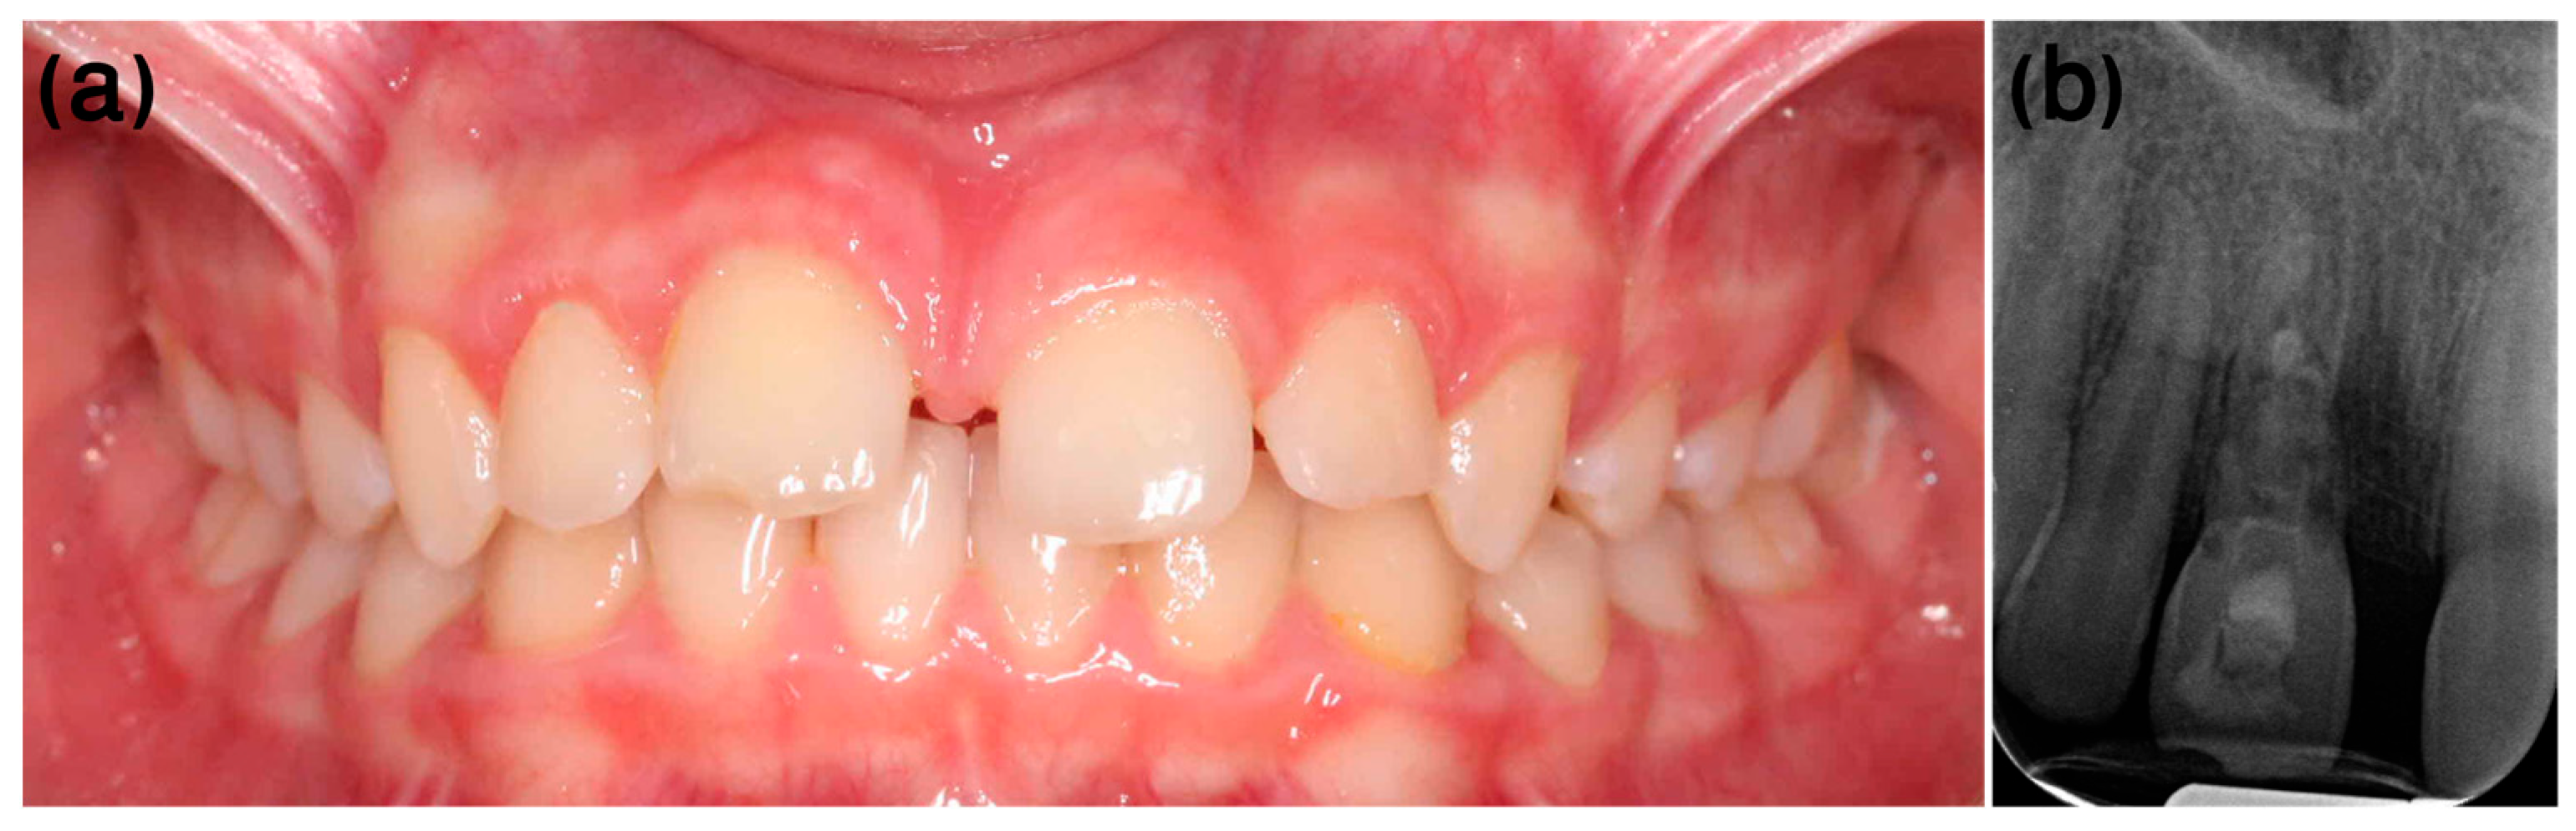

3.1. Case 1

- Dental history